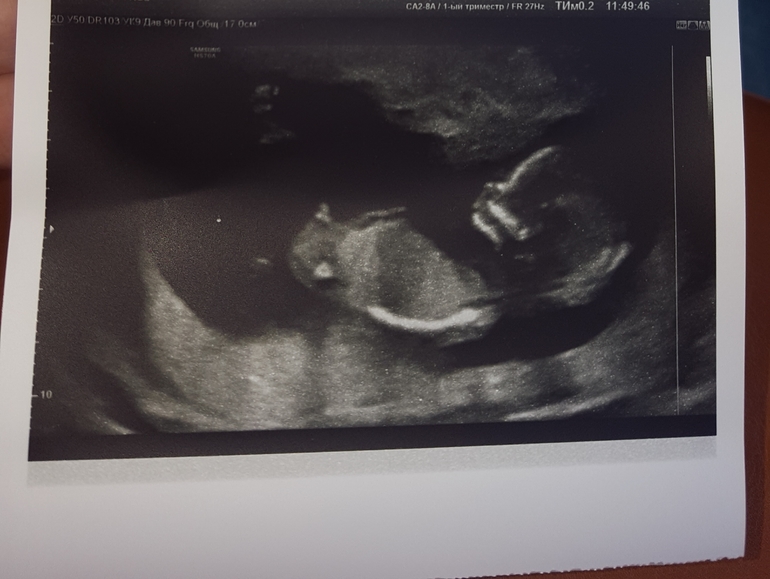

Наконец-то мы сходили на 1й скрининг, увидели своего малыша) он такой миленький🤗 маленький, барахтается там) мне до сих пор не верится что это со мной) я так счастлива) а как обрадовался муж когда врач предположил мужской пол))) ну надеюсь так и будет и ничего не отвалится))! Две дочурки у нас уже есть, так интересно каково это быть мамой мужичка... Я вся в предвкушении) главное чтоб и дальше беременность протекала хорошо, без всяких неприятных неожиданностей... немного волнуюсь за это.

а бугорочек действительно, кажется, мужской